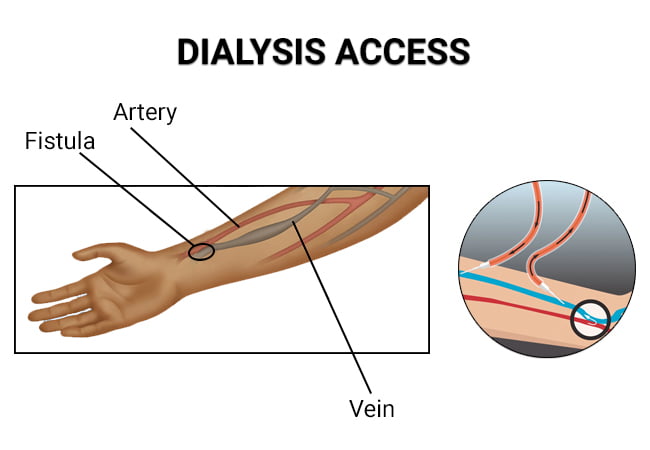

Dialysis Access Interventions